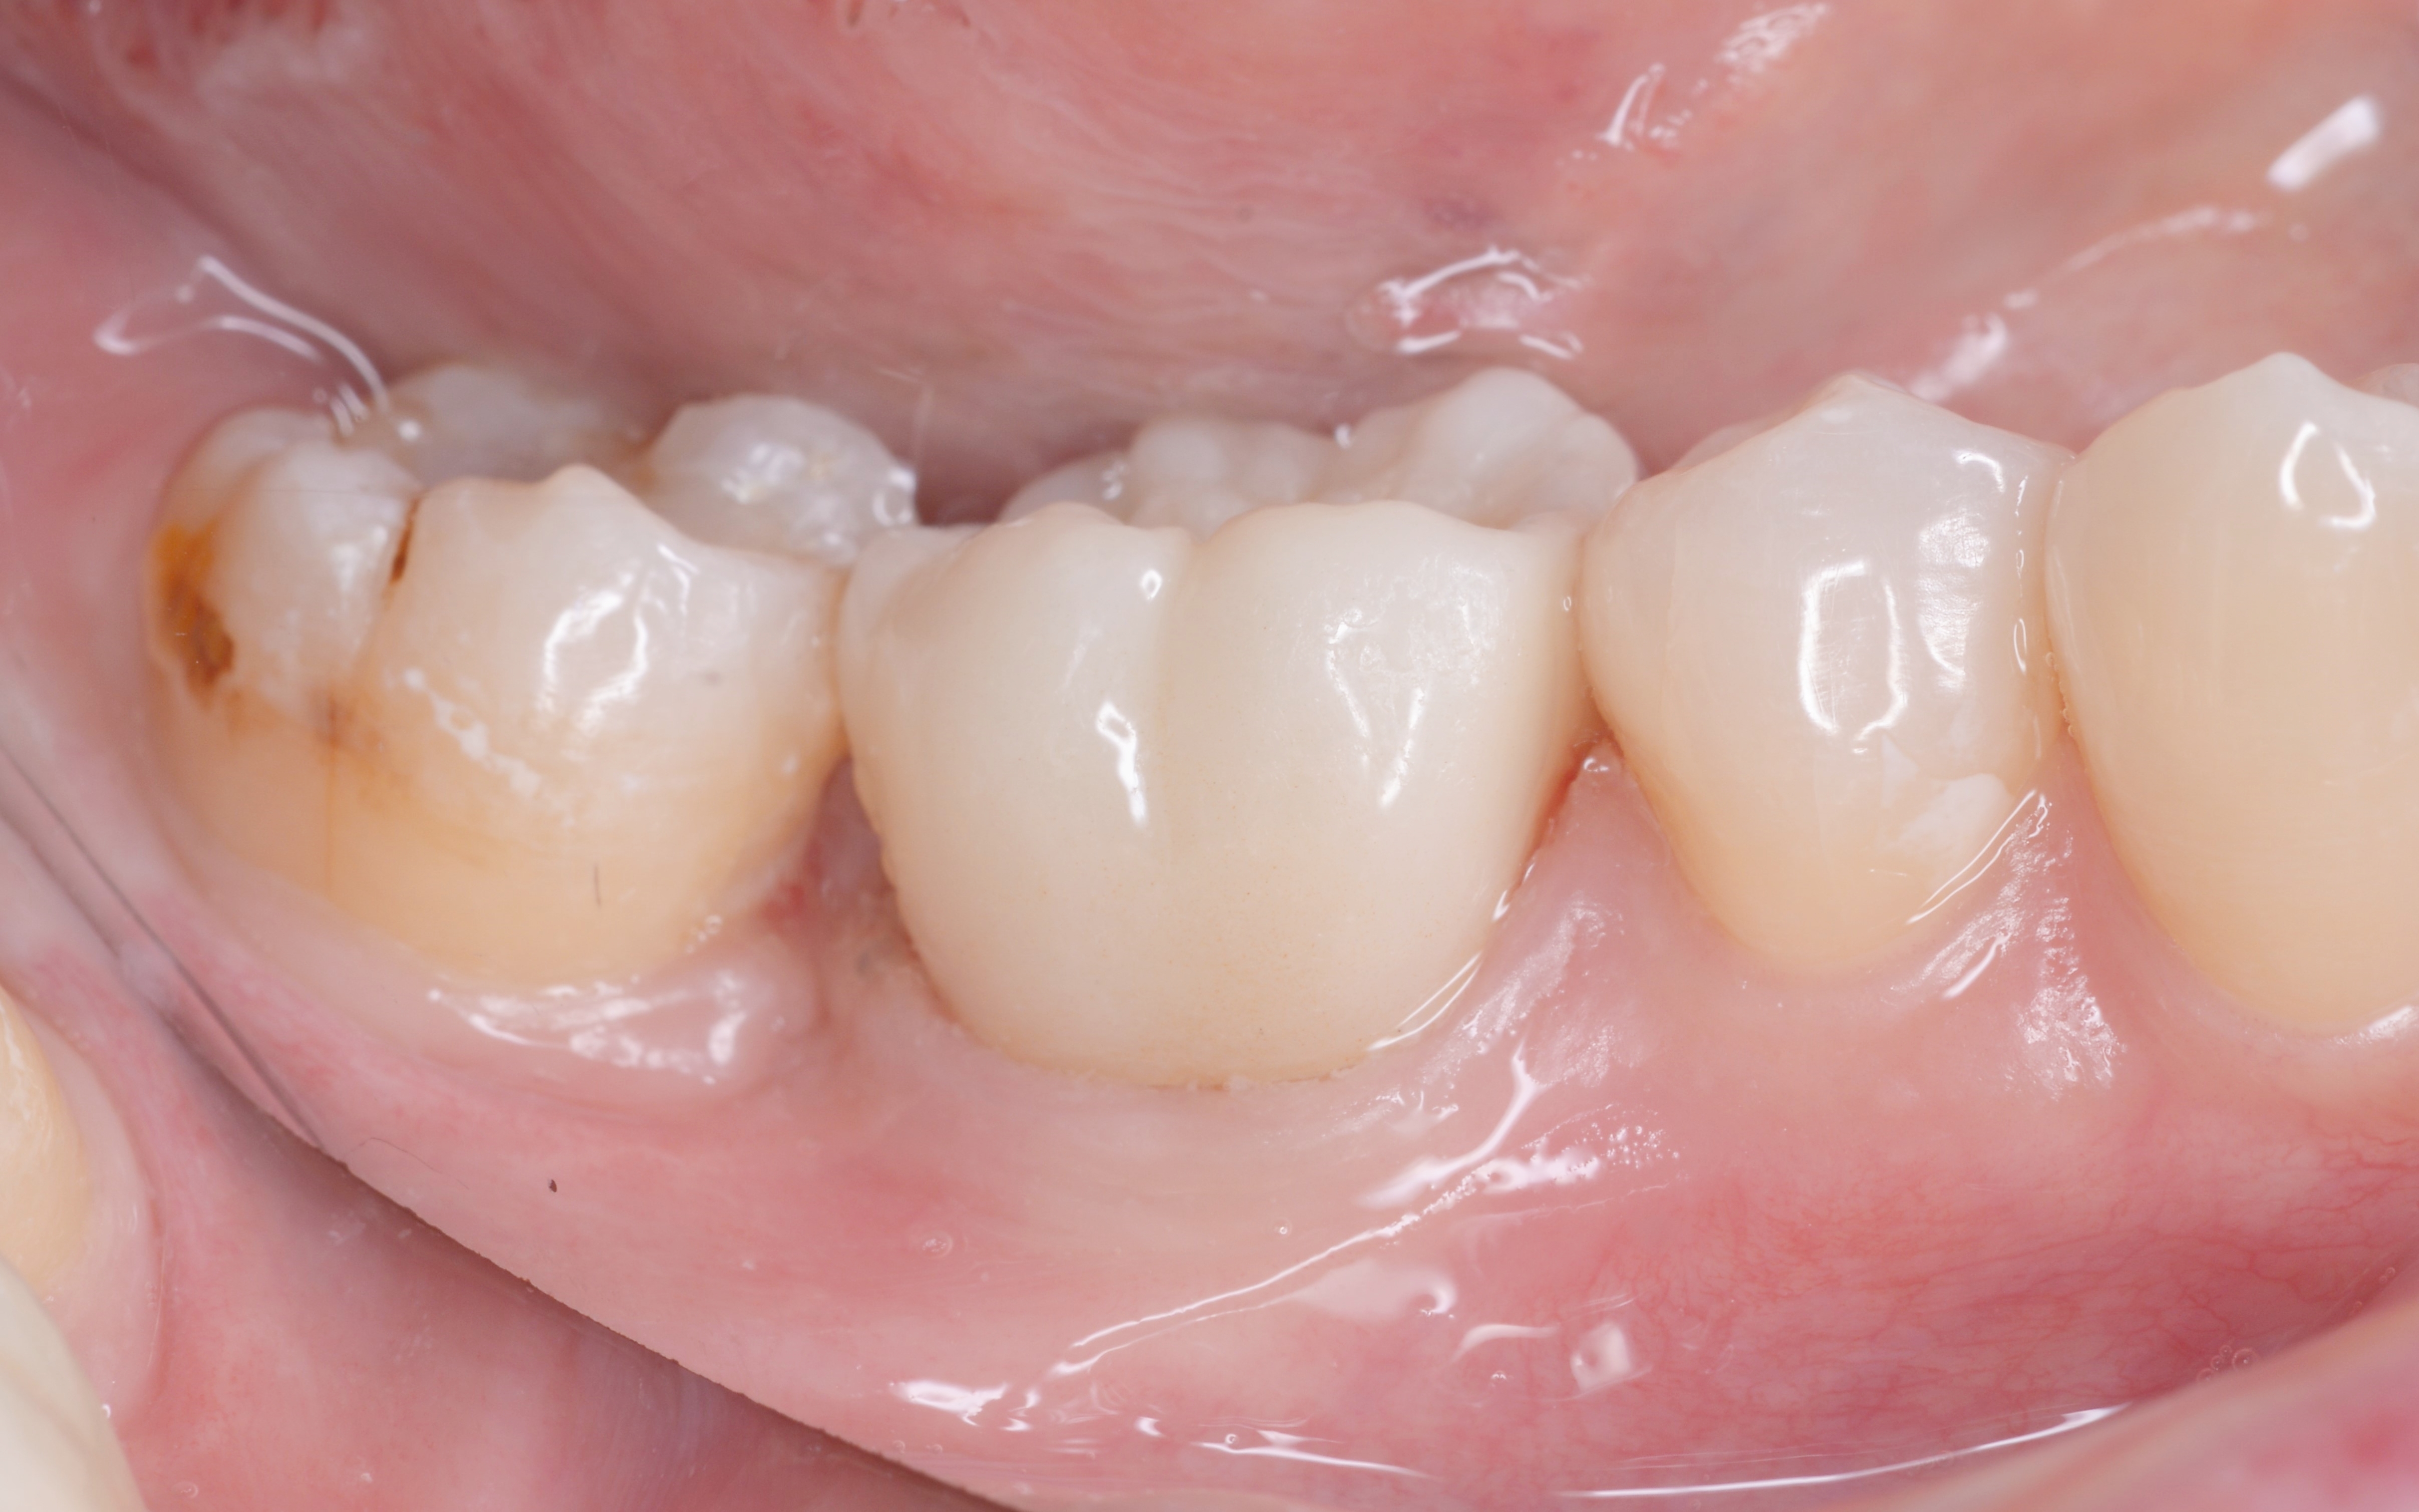

この治療は歯周病の再発リスクを大幅に減らし、長期間安定した状態を保つことができる方法です。 まずは歯周外科手術を行い、歯槽骨を必要な分だけ慎重に除去します。その後、健全な歯質が骨の縁から約3mm上に位置するよう精密に調整し、細菌の侵入を長期間防げる状態に整えました。 手術後は、歯茎と骨の状態が安定するまで経過観察を行い、十分に治癒したことが確認できたあと、顕微鏡を使用した「精密根管治療」を実施します。 続いて、歯の土台となるファイバー支台(ファイバーコア)を作製します。 土台が完成したあとは、被せ物を作製するための精密な型取りを行います。 最後に、完成したジルコニアセラミッククラウンを装着し、噛み合わせや見た目などに問題がないことを確認して、治療を終了しています。 |

精密根管治療を行いました。

精密な型取りを行いました。